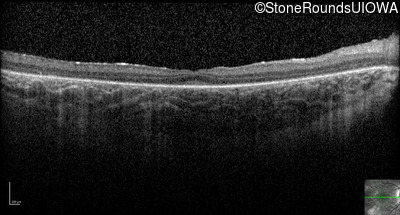

Optical Coherence Tomography - Right - 20/80 -1

Exemplar / OCT Stack